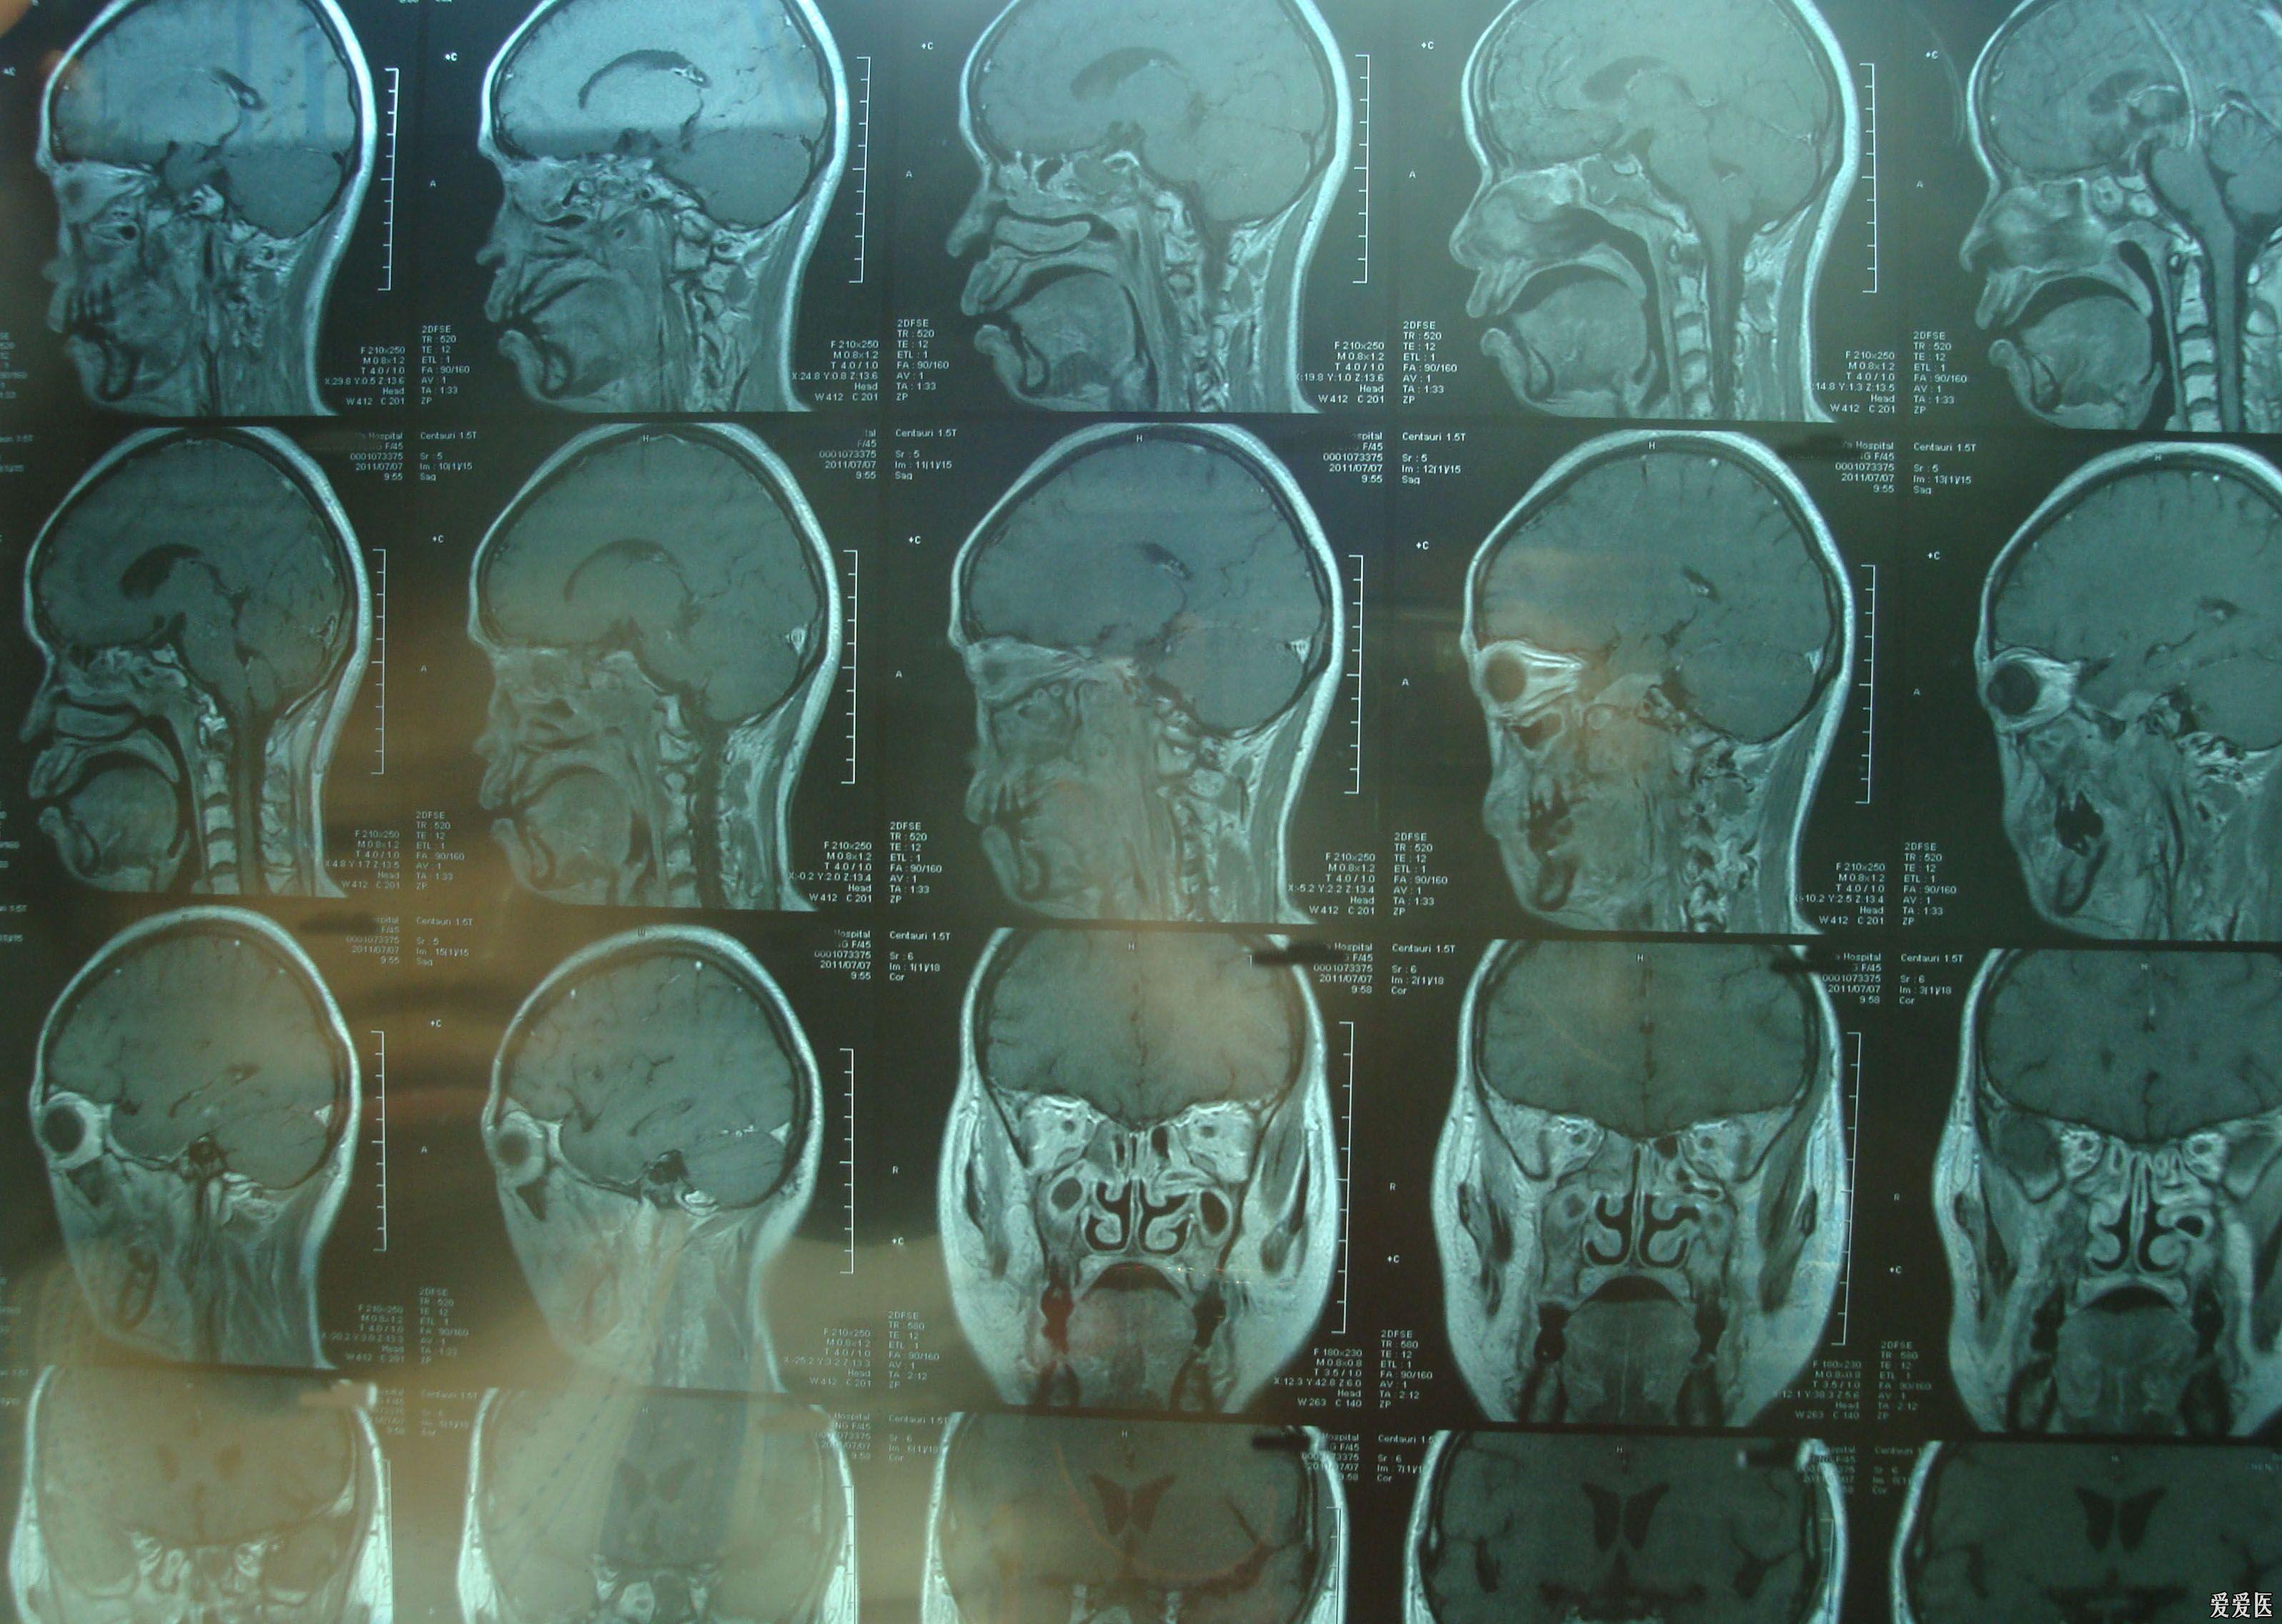

鼻咽癌的mri诊断

图片尺寸960x720